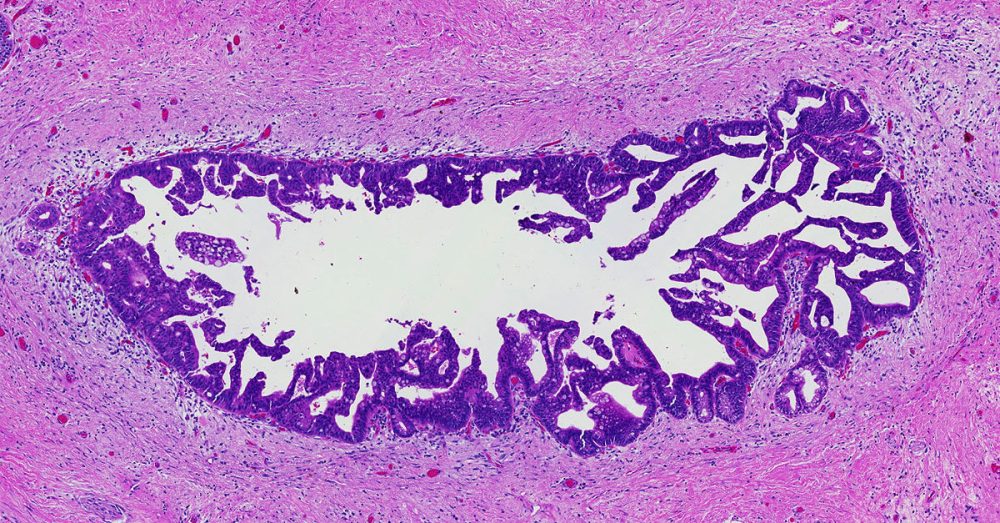

High-grade pancreatic intraepithelial neoplasia replaces the older term- PanIN-3.